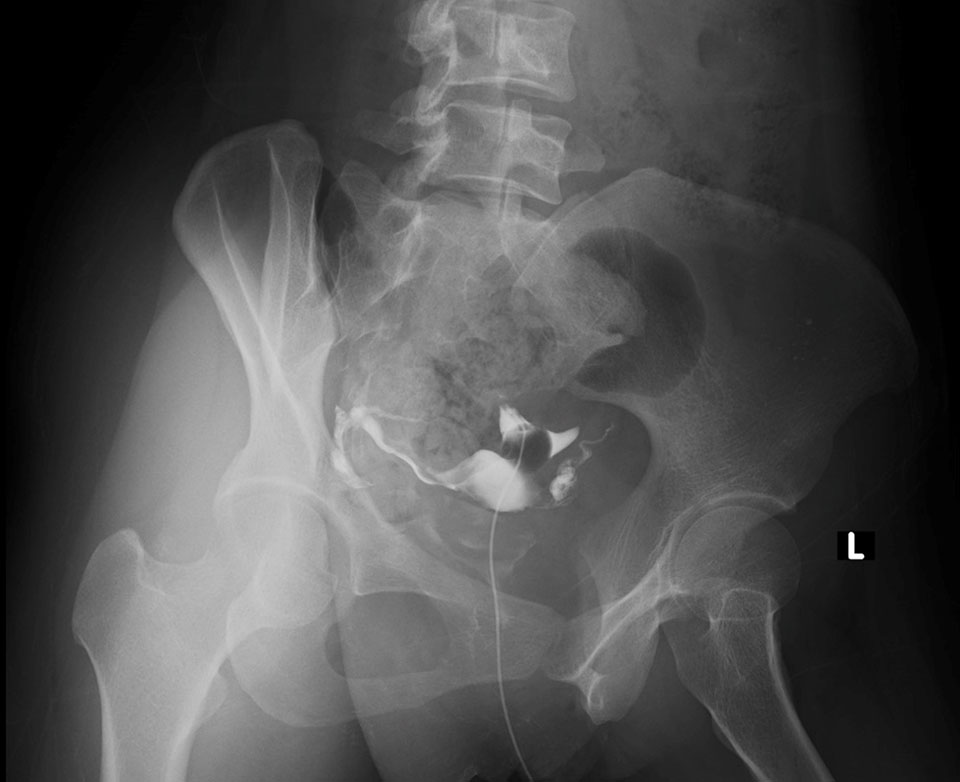

Le produit opaque progressera ensuite, entre le col de l’utérus, la cavité utérine et les trompes de Fallope, permettant ainsi la prise de clichés radiographiques et la visualisation de l’utérus. Cela permet aussi d’observer la perméabilité des trompes ou, au contraire, de leur imperméabilité. On pourra y découvrir la présence d’une tumeur maligne, d’une tumeur bénigne, d’un polype, de tissu… L’hystérosalpingographie est un examen qui dure une trentaine de minutes environ.

Les résultats d’une hystérosalpingographie sont basés sur les clichés et interprétés par le médecin-radiologue responsable de l’examen. Par la suite, un compte rendu écrit à destination du patient et du médecin traitant ou prescripteur sera réalisé. Selon les cas, le médecin peut visualiser une malformation utérine, un fibrome utérin, des polypes… Les trompes utérines peuvent quant à elles être perméables comme imperméables, en raison notamment de la présence de tumeurs malignes, de tumeurs bénignes, de tissu…